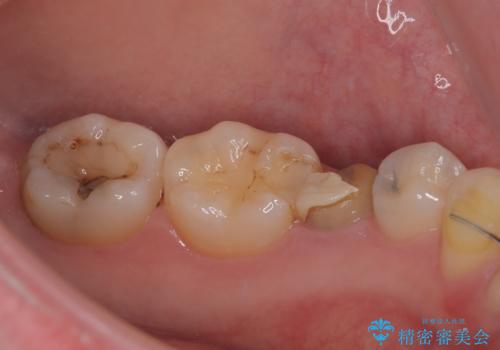

- 左下の被せものが割れたとのことで来院された患者様です。検査の結果、左下の前から4番目の歯はセラミックインレー修復、左下の5番目のところはオールセラミッククラウンによる補綴治療を行っていくことにしました。

拡大鏡視野下で被せもの、虫歯の除去を行い、オールセラミッククラウン、セラミックインレーに適した形に整えました。